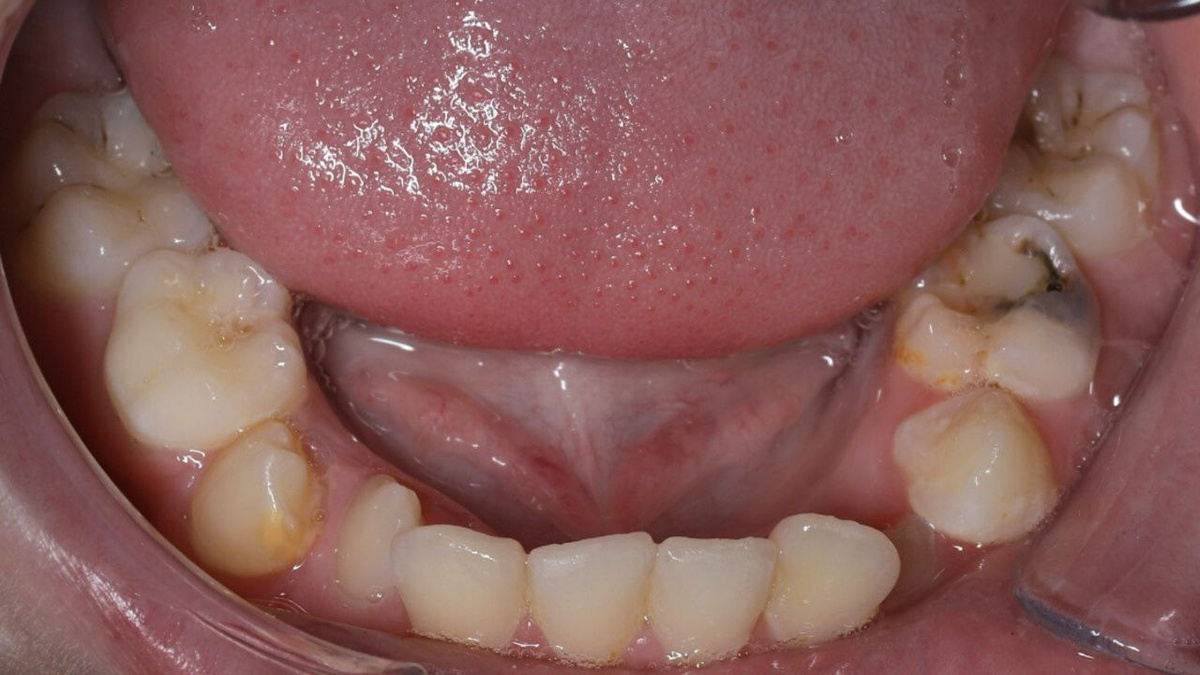

Многие родители замечают, что в период смены прикуса у детей зубы занимают неправильное положение — наклоняются под углом друг к другу, создавая ощущение нехватки места в полости рта. Такую ортодонтическую аномалию называют «скученность зубов», и она является одной из самых частых причин обращений к стоматологу. Почему возникает скученность, можно ли её исправить и к каким последствиям она может привести — рассказала врач-ортодонт клиники «Прайм-стоматология» Шиндяпина Елизавета Васильевна. - Скученное положение зубов — действительно очень распространённая аномалия, при которой нарушается соотношение между величиной челюстей, зубов и их количеством Причин у этой патологии немало: 👉 вредные привычки — закусывание ручки, верхней/нижней губы, сосание пальца, ротовое дыхание могут способствовать неправильному росту и смещению челюстей, деформации зубных рядов. В дальнейшем это нередко вызывает проблемы с жеванием, речью и негативно сказывается на эстетике лица, 👉 полидонтия — наличие св

Многие родители замечают, что в период смены прикуса у детей зубы занимают неправильное положение — наклоняются под углом друг к другу, создавая ощущение нехватки места в полости рта. Такую ортодонтическую аномалию называют «скученность зубов», и она является одной из самых частых причин обращений к стоматологу.

- Скученное положение зубов — действительно очень распространённая аномалия, при которой нарушается соотношение между величиной челюстей, зубов и их количеством

✔ скученность зачастую приводит к ухудшению гигиены полости рта. Что является причиной развития кариеса, заболевания десен (гингивит, пародонтит), а также неприятного запаха изо рта,

✔ могут возникнуть проблемы с прикусом. Неправильное положение зубов затрудняет процесс жевания, неравномерная нагрузка на зубной ряд способствует стираемости эмали, а смещение нижней челюсти, которое может возникнуть из-за скученности зубов, приводит к дисфункции ВНЧС (височно-нижнечелюстной сустав),